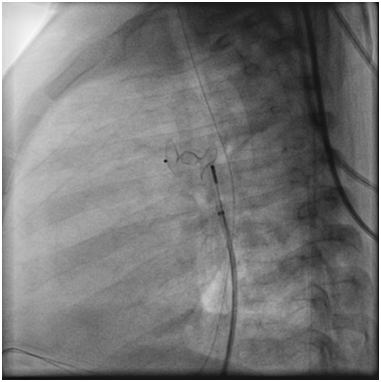

Electrocardiogram was judged to be within normal limits for her age, and her chest roentgenogram showed only slightly increased pulmonary vascularity(Figure 1).

Figure 1 Chest XR showed slightly increased pulmonary vascularity.